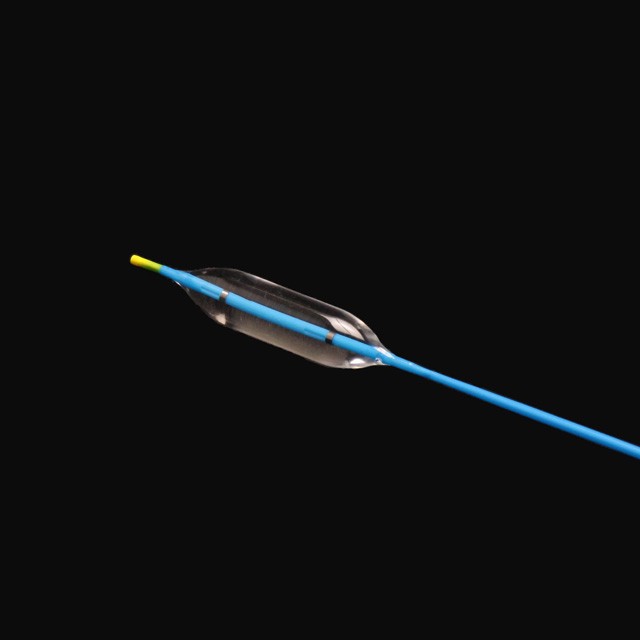

Bul બલૂનને ચોક્કસ દબાણ હેઠળ ત્રણ અલગ વ્યાસ પર સ્નાતક વધારી શકાય છે, ચિકિત્સકો માટે વધુ પસંદગી પૂરી પાડે છે .

● સ્થિતિસ્થાપક સોફ્ટ ટીપ ડિઝાઇન, જે ઓછા નુકસાન સાથે લક્ષ્યની સ્થિતિમાં સરળતાથી પ્રવેશ કરી શકે છે .

The બલૂનના બંને છેડા પર રેડિયોપેક માર્કર્સ એક્સ-રે હેઠળ ચોક્કસ સ્થિતિ પ્રદાન કરી શકે છે .